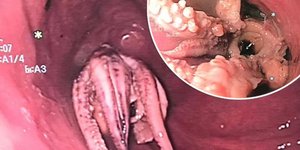

ΕΛΛΑΔΑ 23/03/2025 22:22 Σε νοσοκομείο στην Αθήνα μεταφέρθηκε 38χρονος από το Αγρίνιο που έφαγε χταπόδι με άγκιστρο -Δείτε την ακτινογραφία